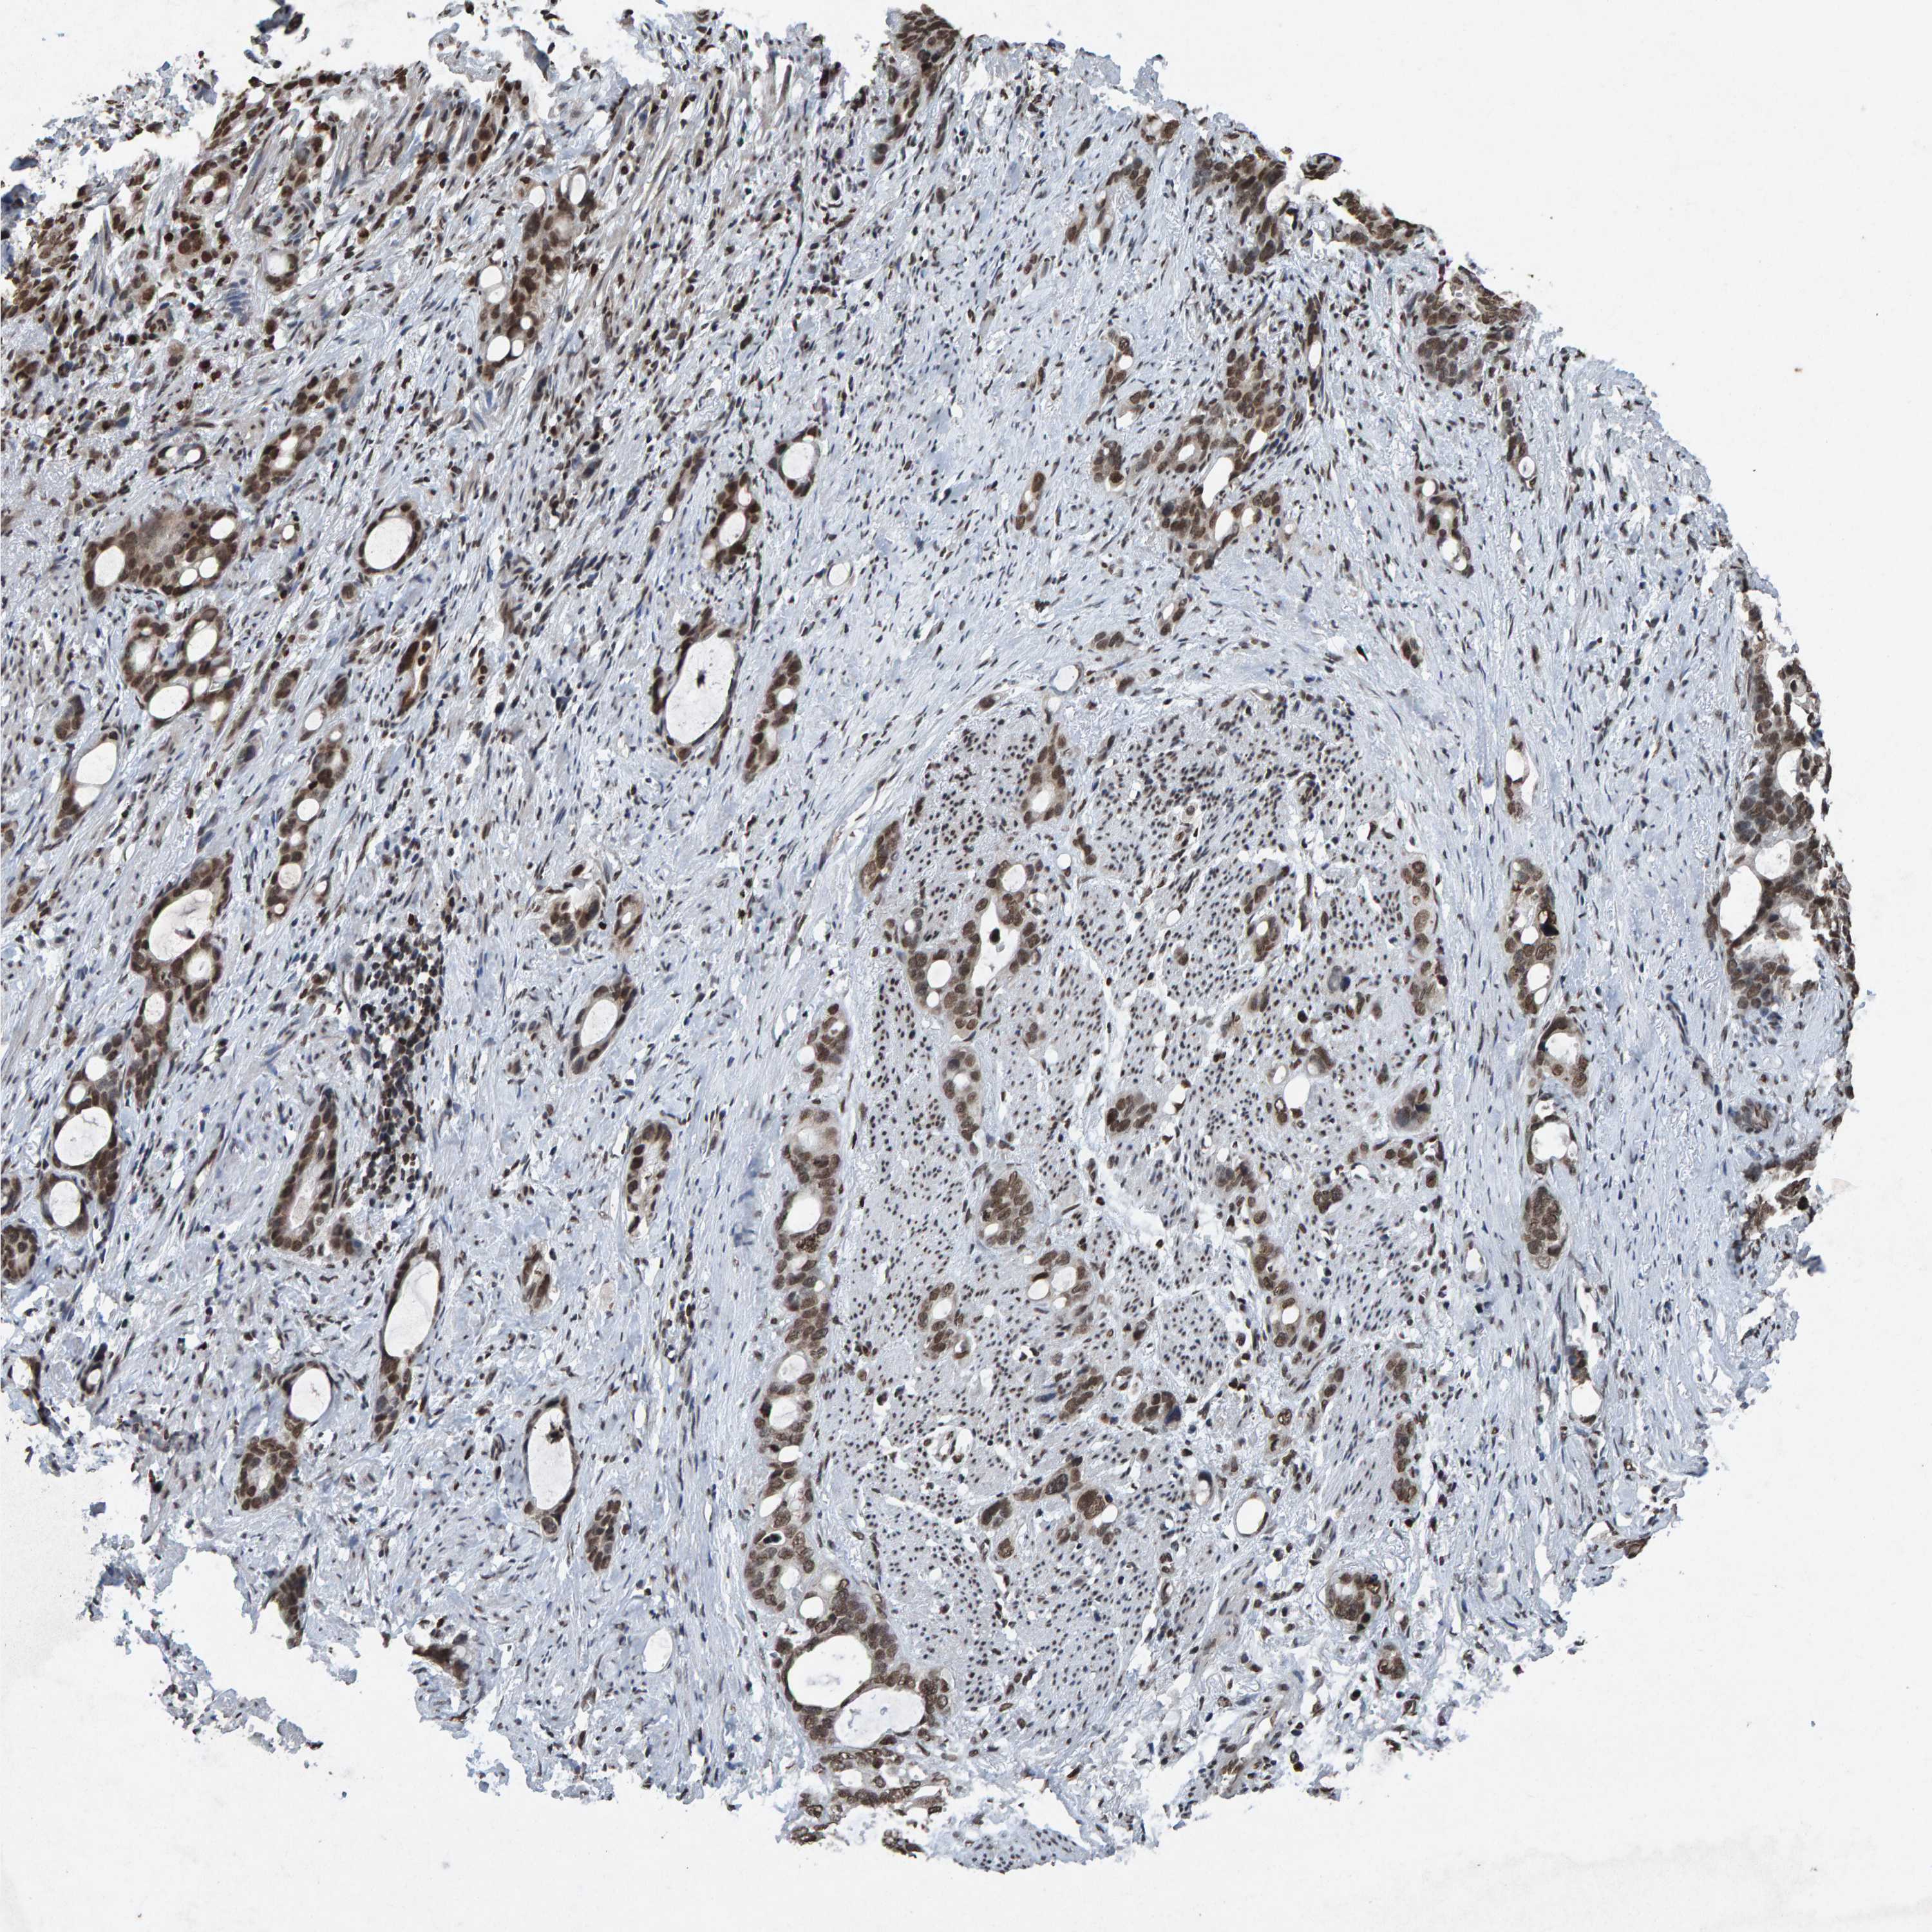

STOMACH CANCER - Protein expressioni

A mouse-over function shows sample information and annotation data. Click on an image to view it in a full screen mode. Samples can be filtered based on level of antibody staining by selecting one or several of the following categories: high, medium, low and not detected. The assay and annotation is described here.

Note that samples used for immunohistochemistry by the Human Protein Atlas do not correspond to samples in the TCGA dataset.

Antibody stainingi

Antibody staining in the annotated cell types in the current human tissue is reported as not detected, low, medium, or high, based on conventional immunohistochemistry profiling in selected tissues. This score is based on the combination of the staining intensity and fraction of stained cells.

Each image is clickable and will lead to virtual microscopy that enables deeper exploration of all samples and also displays staining intensity scores, fraction scores and subcellular localization as well as patient and tissue information for each sample.

Antibody HPA057236

Antibody CAB022549

Staining

High

Medium

Low

Not detected

Intensity

Strong

Moderate

Weak

Negative

Quantity

>75%

75%-25%

<25%

None

Location

Nuclear

Cytoplasmic/membranous

Cytoplasmic/membranous,nuclear

Adenocarcinoma, NOS

Adenocarcinoma, High grade